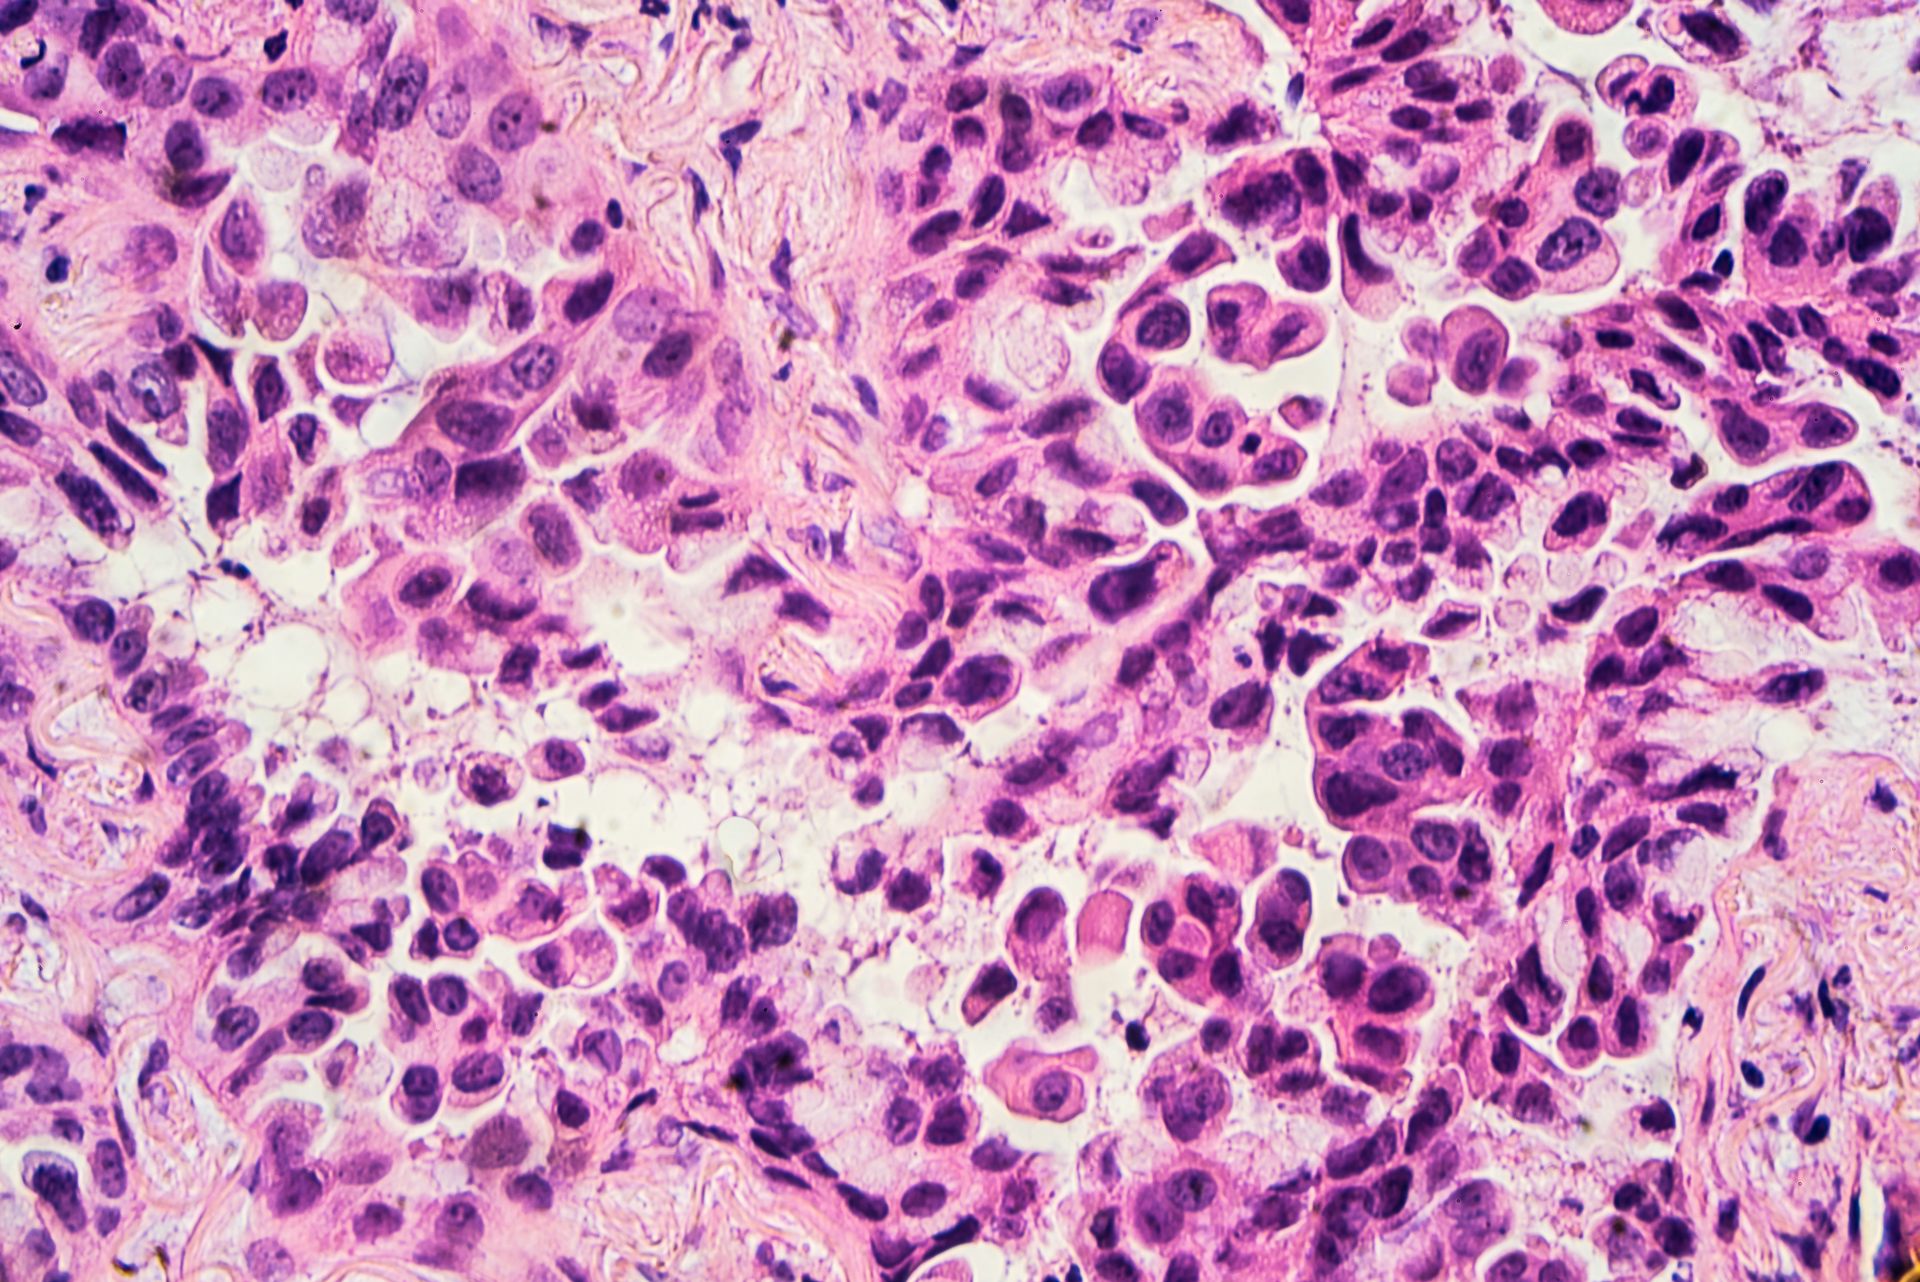

Гистологический срез плоскоклеточного рака — одного из подтипов немелкоклеточного рака легкого

Изображение: librepathology.org